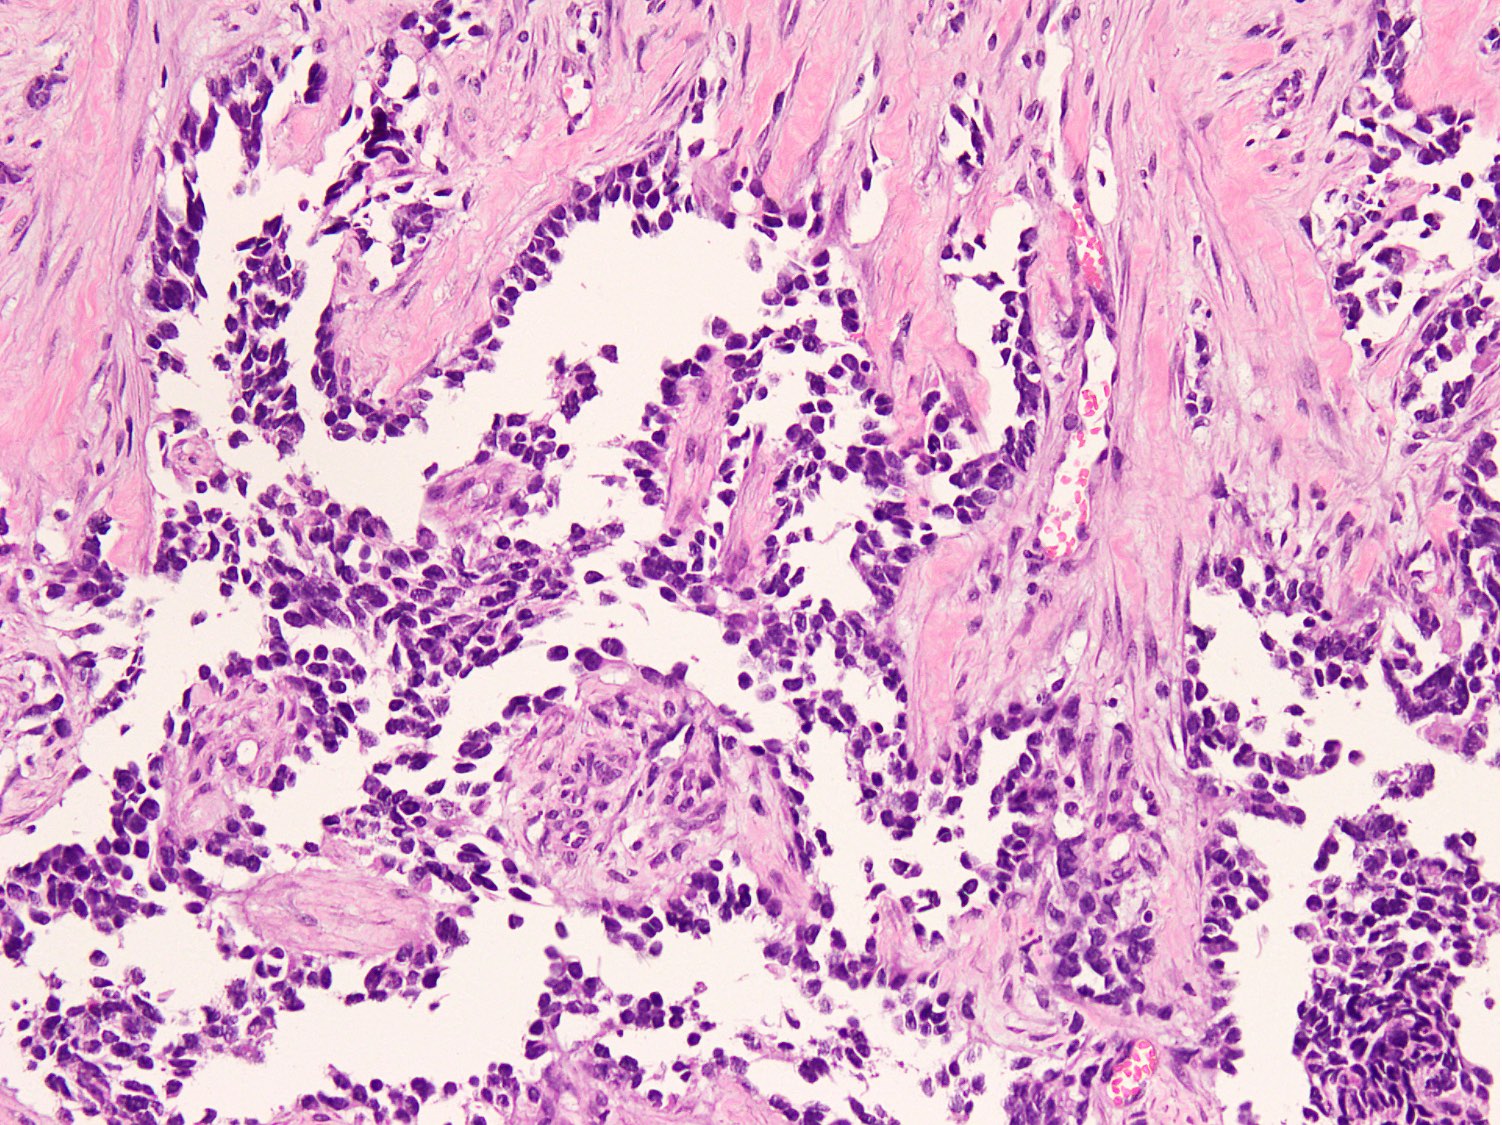

Microscopic (histologic) description

- Cellular round cell tumor

- Large clusters, nests, cords and trabeculae of primitive round cells, separated by variably thick fibrovascular septa

- Loss of cellular cohesion in the center forms alveolar-like, cystic and vague papillary appearance (Histopathology 2022;80:98)

- Layer of cells adheres to the periphery of the spaces and fibrous septa

- Small to intermediate sized monomorphic cells with scant cytoplasm

- Hyperchromatic nuclei with variable conspicuous small nucleoli

- Cells in the center have poor preservation and are necrotic; may appear floating

- Multinucleated tumor giant cells with wreath-like lineup of nuclei are common (Acta Pathol Microbiol Immunol Scand A 1982;90:345)

- Round to oval rhabdomyoblasts with abundant acidophilic cytoplasm may be present

- Brisk mitosis and variable tumor necrosis

- Occasional cases may show clear cell morphology with pale, glycogenated cytoplasm

- Rare anaplasia

- Some cases may show histologic features of embryonal rhabdomyosarcoma; molecular studies are essential to characterize such cases (Am J Clin Pathol 2013;140:82)

- Solid variant:

- Sheets of neoplastic cells

- Lack fibrovascular septa, pseudoalveolar spaces and dyscohesion (Cancer Genet Cytogenet 2005;163:138)

- May show rhabdomyoblastic differentiation

- Abundant mitotic activity

Microscopic (histologic) images

Contributed by Nasir Ud Din, M.B.B.S.